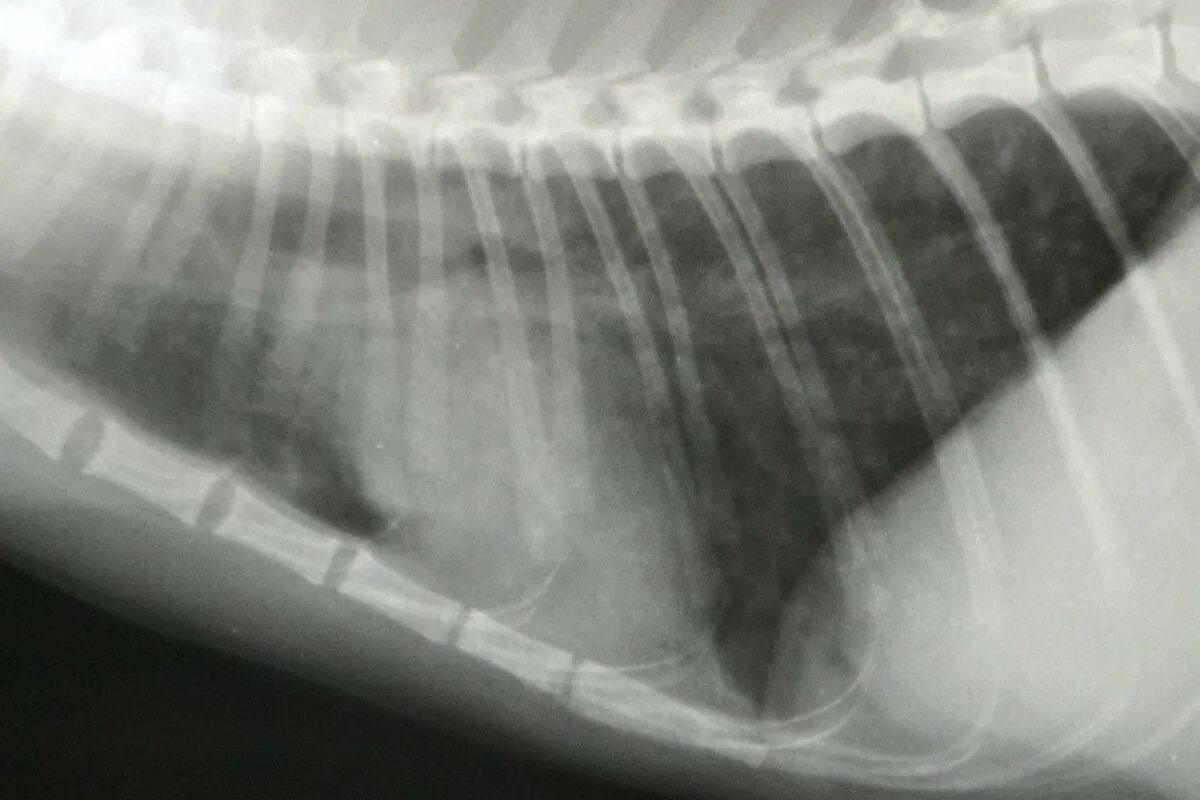

Астма у кота